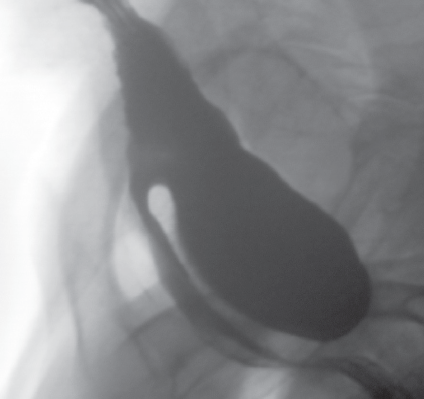

This article features a collection of photo-based cases of gastrointestinal disorders including zenker diverticulum, duodenal adenocarcinoma, and strongyloidiasis.